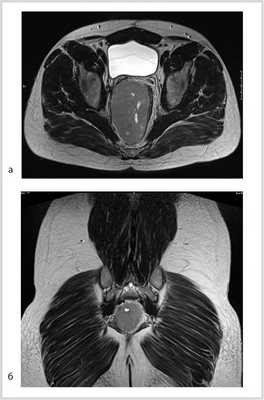

Рис. 3. МР-томограммы малого таза. Опухоль уменьшилась в размере до 5,5×3,5×4 см, однако тесно прилежит к правой стенке прямой кишки. а — аксиальный срез; б — сагиттальный срез; в — фронтальный срез.

В отделении проведен повторный консилиум с участием химиотерапевтов саркомной группы, хирургов сакральной группы, а также сотрудников отделения онкопроктологии. Учитывая нерадикальность предыдущей операции по поводу неэпителиальной опухоли малого таза, положительную динамику на фоне полихимиотерапии в виде уменьшения размера опухоли (более чем в два раза), а также молодой возраст пациента, принято решение вторым этапом выполнить оперативное вмешательство в объеме цилиндрической (экстралеваторной) брюшно-промежностной экстирпации прямой кишки, предложенной австрийским хирургом Т. Holm в 2007 г.